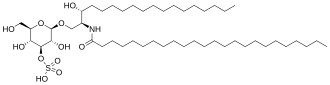

Метахромати́ческая лейкодистрофи́я (англ. Metachromatic leukodystrophy (MLD), также сульфати́дный липидо́з) — редкое наследственное заболевание из группы лизосомных болезней накопления с аутосомно-рецессивным механизмом наследования нарушения обмена веществ[1]. Данная нозологическая единица из разряда лейкодистрофий (патология роста и/или развития миелиновой оболочки, покрывающей большинство нервных волокон центральной и периферической нервной системы) относится к сфинголипидозам. Характеризуется недостаточностью арилсульфатазы А[2] (цереброзидсульфатазы) — фермента лизосом, участвующего в метаболизме сфинголипидов, что вызывает накопление цереброзида сульфата[1][3].

Метахроматическая лейкодистрофия развивается в результате дефицита лизосомного фермента арилсульфатазы А (АРСА, англ. ARSA)[2] или цереброзидсульфатазы. На фоне развёртывания клинической симптоматики уровень активности фермента в лейкоцитах существенно снижается и составляет менее 10 % от нормальных величин[6]. Тем не менее, одного анализа активности цереброзидсульфатазы недостаточно для верификации диагноза. Описана форма псевдо дефицита АРСА (англ. ARSA pseudo deficiency), при которой активность фермента составляет от 5 до 20 % от нормы и при этом отсутствуют признаки метахроматической лейкодистрофии[6]. На фоне дефицита или недостаточности фермента происходит накопление сульфатида во многих тканях организма, что в конечном счёте приводит к разрушению миелиновой оболочки нервных волокон. Миелиновая оболочка — липидное покрытие нервного волокна, которое не только защищает его, но и способствует повышению скорости проведения импульса по нерву. Потеря миелина центральной нервной системой (мозг) и периферической нервной системой нарушает систему контроля и снижает мобильность мышц, таким образом нарушая их функцию.

Согласно проведенному исследованию утверждается, что накопление сульфатида не вполне отвечает клинической картине метахроматической лейкодистрофии ввиду своей нетоксичности. В связи с этим высказано предположение, что клинические признаки развиваются на фоне накопления лизосульфатида (метаболита сульфатида, лишённого ацильных групп), вещества обладающего цитотоксическими свойствами in vitro[8].